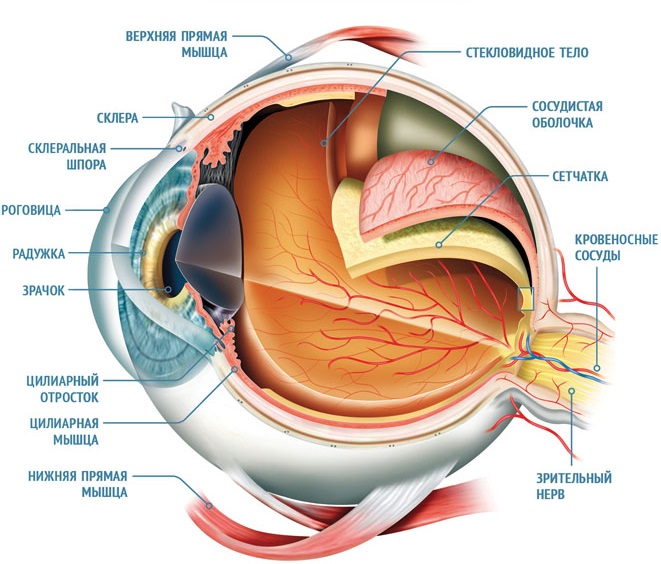

КТ-графики и изображение строения глаза